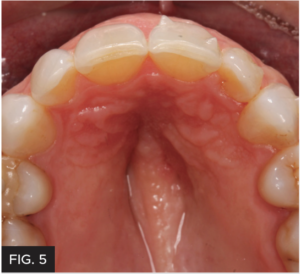

CLINICAL EXAMINATION AND FINDINGS

Examination and images, including the prescribed series of AACD photographs,2 revealed that #7 was normal, but smaller in crown size than ideal. Some tissue inflammation, likely related to orthodontic attachments, was visible on the tooth’s distal surface.The photographs and clinical data were reviewed with the patient. The main esthetic challenge would be to recreate incisal translucency and characteristics. (FIG 1 & 2)